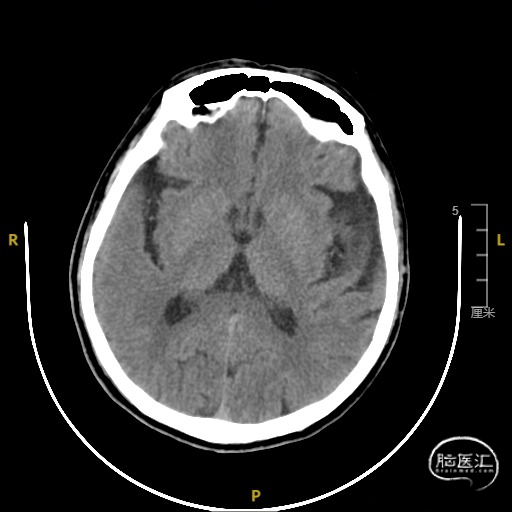

➢ 门诊头CT检查

➢ 入院后头核磁检查